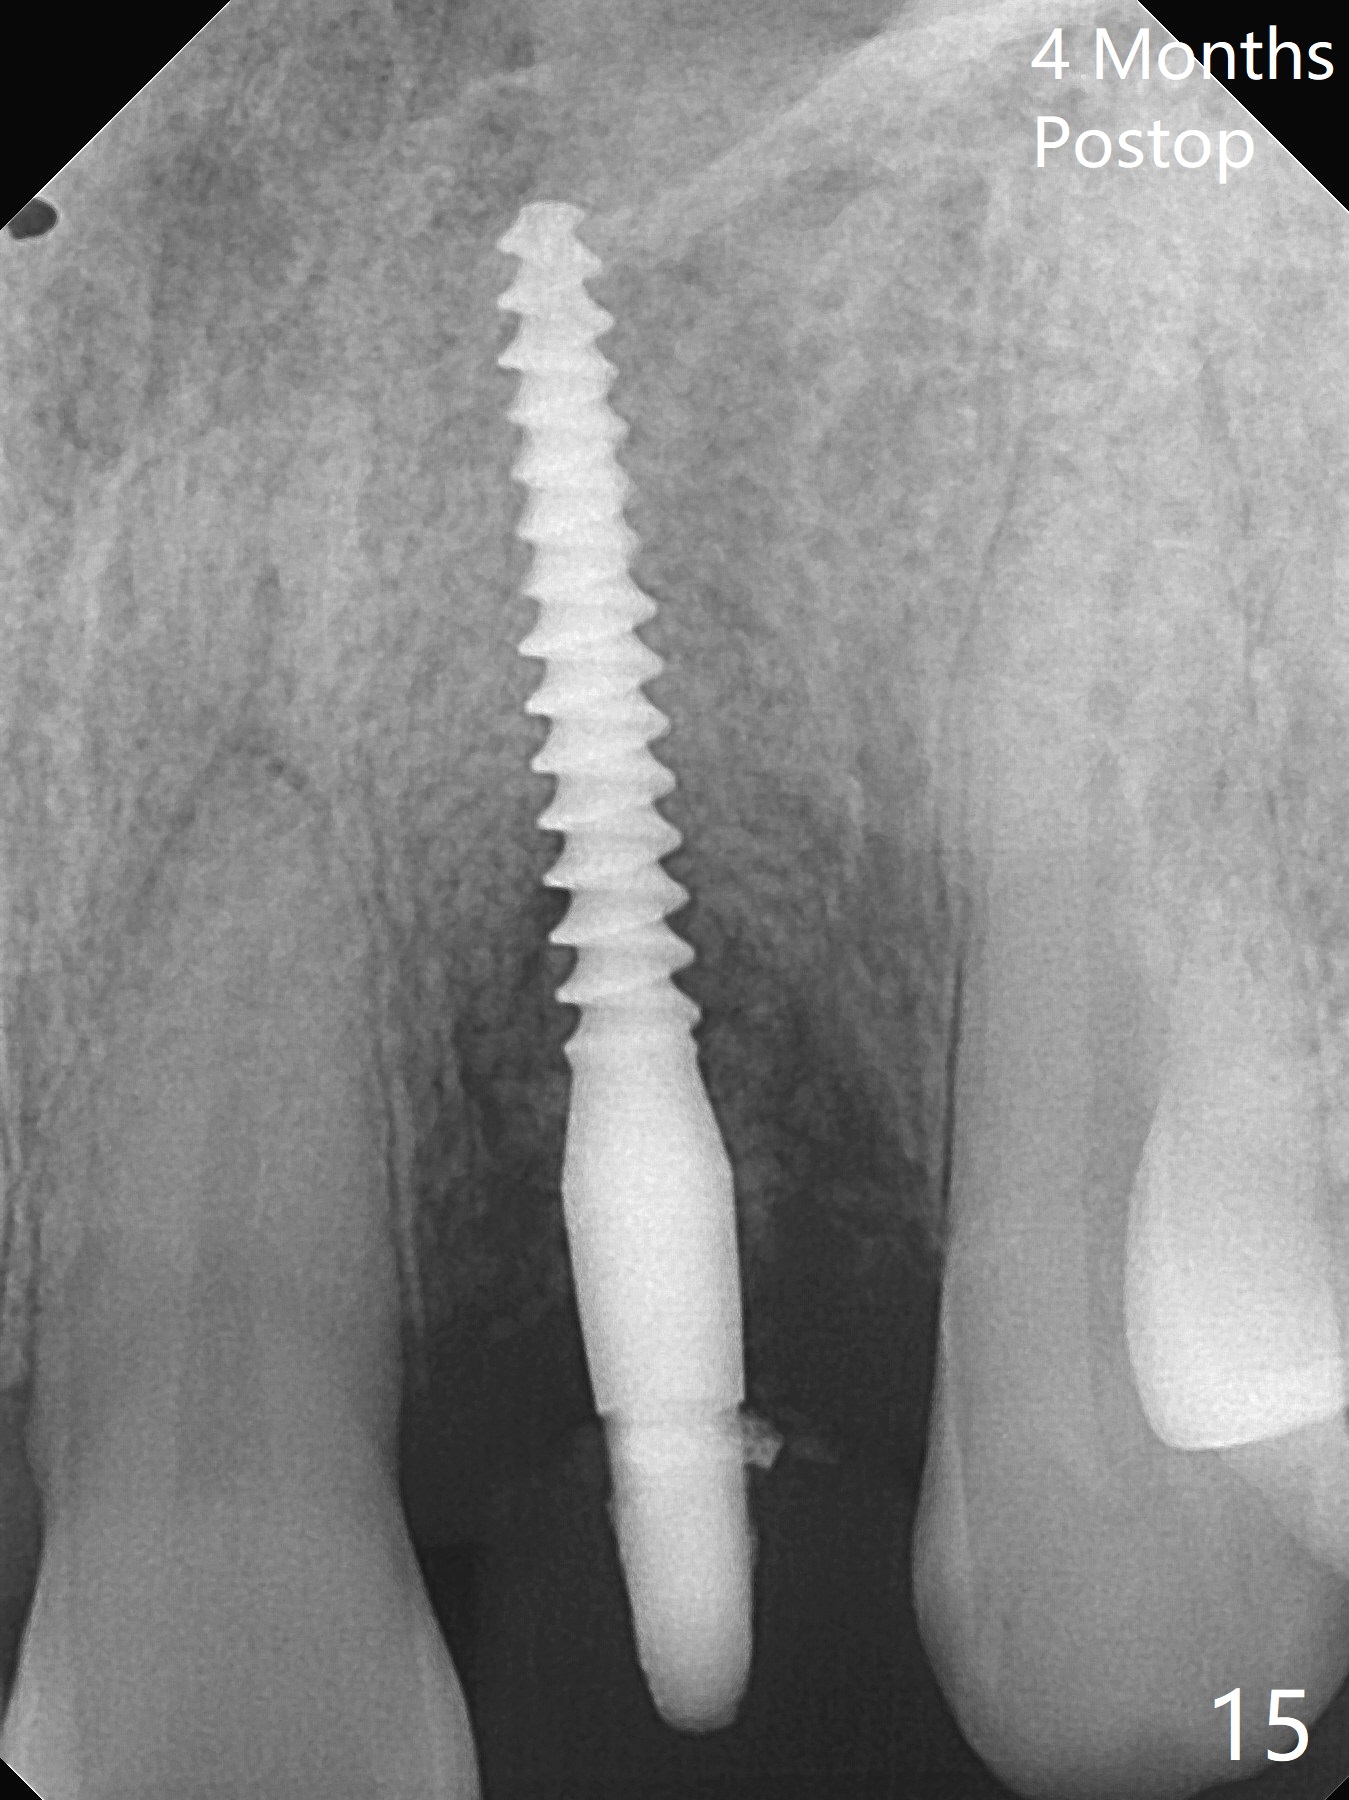

病人回来带来瘘道(图一),不过不会增加难度,病牙去除,它便自动消失。尽管颊侧骨壁完全失去,颊侧牙龈仍丰满(图二),为什么呢?第一,因为粗大牙根存在,第二两旁牙齿,牙槽骨撑着帐篷(侧切牙颊侧牙龈),第三,牙冠。为了防止术后牙龈塌陷,尽量不切开,即刻放置植体(牙根);由于前牙缘故,这次植体不能很大,所以植骨必须过度(over grafting),最后即刻制作临时牙冠,撑住牙龈。这就是所谓每个人进入角色。这个牙根有一种先天性畸形:dens in dent (图三(腭侧观):箭头)。尽管腭侧牙根畸形,腭侧骨壁吸收临床上并不严重,所以钻洞仍偏腭侧。当预定最后钻头还在钻洞时,填入大量粘性骨块(图四:*),细长植体还没有完全卡入鼻底(图五),最后好像可以(图六,七)。植体,骨粉入位(图八),最后临时牙冠出场(图九)。尽管植体小,术后一周临时牙冠仍然可以维持牙龈原有形状(emergency profile,图十:箭头(*:树脂强化牙冠固定))。图十一以不同角度显示瘘道缩小。术后三周取出有些松动的临时牙冠,骨粉虽然还没有被肉芽组织整合,但是显得正常,周围牙龈健康(图十二)。术后4个月牙龈形态正常(图十三),没有触痛;颊侧骨板轻度凹陷(图十四);骨粉仍在原位(图十五)。术后7个月骨粉仍在原位(图十五,十六,但是冠部密度减低(可能骨粉流失,需要牙周或者树脂敷料保护)),没有螺纹暴露。但是牙冠边缘暴露,说明牙龈收缩(图十七,与图十三对比),颊侧骨板仍塌陷(图十八)。插入龈线取得多个目的:修整基台边缘,取模,颊侧牙龈推向颊侧,有利于即将衬里牙冠龈缘进入龈下(图十九)。取模后牙冠边缘(图二十:<)衬里,然后修整,变窄,以便插入龈下,促进颊侧牙龈下降(图二十一,二十二)。术后8个月牙冠粘固前牙龈健康(图二十七,八),牙冠(图二十九)固位后,病人满意(图三十),咬合调整(图三十一),注意腭侧粘固粉流出通道(<)。